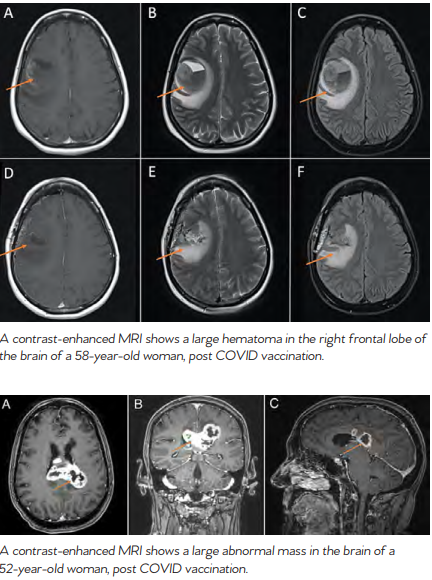

Even with anti-vaccine sentiment and vaccine concerns, the origins of vaccines do seem to make a great case for themselves, and modern science backs this up. According to the National Foundation for Infectious Diseases, The US has a robust approval process to ensure that all licensed vaccines are safe. They say that potential side effects associated with vaccines are uncommon and much less severe than the diseases they prevent. According to the CDC, getting all recommended vaccinations is a powerful step in taking charge of your health. They say that when given as directed, FDA-authorized vaccines can prevent severe disease and save lives. WHEN HARM IS CAUSED BY VACCINES When vaccines first began to be widely used, people who experienced serious side effects from vaccination had little recourse to compensation from manufacturers, physicians or the government. This was particularly a problem when vaccine production techniques were in their infancy, and contamination of vaccines occasionally occurred during or after manufacture. Since the passage in 1902 of the U.S. Biologics Control Act, which initiated the regulation of vaccines, such problems with negligence in manufacturing have greatly declined. As product liability law evolved during the 20th century, it eventually provided an avenue for compensation for individuals harmed by vaccines — they could sue vaccine manufacturers or they could sue physicians who administered vaccines. To help keep track of adverse reactions to vaccinations, the CDC and the FDA established The Vaccine Adverse Event Reporting System (VAERS) in 1990. According to the CDC, VAERS is used “to detect possible signals of adverse events associated with vaccines.” About 30,000 events are reported each year to VAERS. Between 10% and 15% of these reports describe serious medical events that lead to hospitalization, lifethreatening illness, disability or death. COVID VACCINES According to the National Foundation for Infectious Diseases, as of April 15, 2022, 19 vaccines have been authorized for emergency use and 12 given full approval for use. In 2020, the FDA authorized two mRNA COVID vaccines for emergency use. In 2021, the FDA approved the Pfizer-BioNTech COVID-19 vaccine for people ages 16 and older, and following that, the Pfizer-BioNTech vaccine for children ages 5 through 15. In 2022, the FDA approved the Moderna COVID-19 vaccine, now called Spikevax, for people age 18 and older. Researchers continue to study and develop several other COVID-19 vaccines. It’s estimated that COVID-19 vaccination results in a low risk of another infection with a similar variant for at least six months. HOW COVID VACCINES WORK According to the CDC, COVID-19 vaccines work with your immune system so your body will be ready to fight the coronavirus if you are exposed to it — including coronavirus variants. In addition, COVID-19 vaccination might offer more protection than becoming infected with COVID-19. A recent study has shown that unvaccinated people who already had COVID-19 are more than twice as likely as fully vaccinated people to be reinfected with COVID-19. Recent research also suggests that people who got COVID-19 in 2020 and then received mRNA vaccines produce very high levels of antibodies that are likely effective against current and possibly future variants. Some scientists call this hybrid immunity however further research is needed to confirm this phenomenon. DO COVID VACCINES EFFECT THE BRAIN? Though cases of neurologic symptoms related to COVID vaccination are uncommon, they are not unheard of. Two cases, published in the Cureus Journal of Medical Science, show that neurological inflammatory responses and the presence of neurooncologic lesions are possible after COVID vaccination. The journal describes two patients that presented with neurologic deficits that were not present prior to being vaccinated. One of the cases presented in the article was of a 58-year-old woman who experienced high-grade fevers, slurred speech and facial droop approximately two weeks following her second dose of a COVID-19 vaccine. According to the journal, the patient’s symptoms were attributed to post-vaccination Bell’s Palsy. Her fevers resolved over the next 24-48 hours as is typical with post-vaccination symptoms, however facial weakness persisted until approximately two weeks later when she developed acute

worsening of her facial droop with associated slurred speech, drooling as well as left arm and leg weakness. A contrastenhanced MRI of the brain demonstrated a large hematoma in the right frontal lobe. The patient underwent surgery to remove the hematoma. The second case presented in the journal was of a 52-yearold woman who developed severe headache and neck stiffness associated with intermittent high-grade fevers four days after her first dose of a COVID-19 vaccine. Contrast-enhanced MRI scans showed an abnormal mass on her brain. RISK VS. REWARD Despite this evidence of COVID vaccines effecting the brain, studies have shown that adverse events after COVID vaccination are rare and many COVID vaccines have proven over 90% effective with no safety threat. Additionally, other studies have shown that brain health may be more at risk after COVID infection than after vaccination. Whether or not to receive a COVID-19 vaccination is a personal decision, however, it is important to be aware of the potential adverse effects.